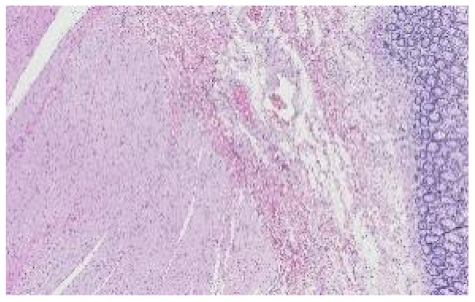

In the data collection phase, we obtained H&E-stained slides used in an external quality assessment (EQA) round organized by Labquality (Helsinki, Finland), a company providing external quality assessment schemes for clinical laboratories. The slides had a tissue microarray section consisting of three 6 mm punch biopsies. The punches were taken from normal human kidney, skin, and colon samples. The samples were anonymous formalin-fixed and paraffin-embedded routine histologic samples from a reference pathology laboratory. The EQA round was organized such that unstained 3 µm sections were sent to laboratories participating in the EQA scheme. The laboratories were asked to stain the slides by the H&E method they use in their daily practice. Altogether 66 laboratories from 11 countries returned the slides for the assessment. After that, the slides were digitalized with a NanoZoomer-XR (Hamamatsu Photonics) slide scanner with a 20× objective (scanning resolution 0.46 μm/pix); Figure 1 shows a random example of a stained slide.

Figure 1.

Randomly chosen WSI, label 1 for kidney, 2 for skin, and 3 for colon tissue.